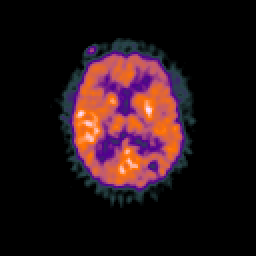

Glioma overlay -- Slice #65

[Home][Help][Clinical] Slice 65